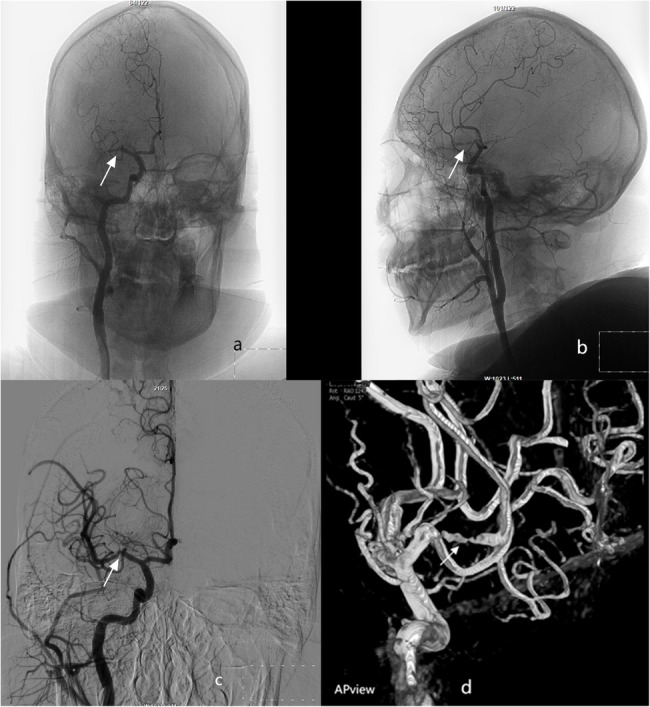

Case description: A pediatric patient presented with AIS involving the left limb, lasting 2.5 h. The stroke occurred during physical activity without loss of consciousness or seizures. Head magnetic resonance imaging (MRI) combined with clinical manifestations confirmed the diagnosis of acute cerebral infarction. Intravenous thrombolytic therapy using tenecteplase was initiated in the ultra-early phase of infarction. Subsequent cerebral angiography revealed occlusion of the superior trunk of the right middle cerebral artery. Three-dimensional rotational imaging identified multiple aneurysms at its bifurcation. A targeted intra-arterial injection of tirofiban (6 mL) was administered to stabilize plaque and enhance blood flow. The patient underwent 11 days of antiplatelet therapy and supportive care. At the 90-day postoperative follow-up, notable recovery of limb function was observed.